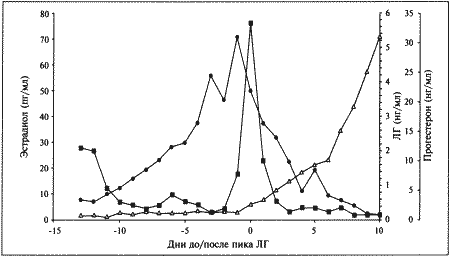

Фиг. 1.1.

Изменения концентрации эстрадиола (●), лютеинизирующего гормона (ЛГ,) и прогестерона (∆) в сыворотке крови у сук. На графике за точку отсчета принят день пика концентрации ЛГ. Следует отметить, что пик концентрации эстрадиола приходится на день минус 1, уже на день 0 заметно повышение концентрации прогестерона. (Перевод единиц: 1 пг/мл эстрадиола = 3,6 пмоль/л; 1 нг/мл прогестерона = 3 нмоль/л)

Стадия проэструса характеризуется развитием фолликулов под влиянием гонадотропных гормонов — лютеинизирующего (ЛГ) и фолликулостимулирующего (ФСГ), выделяемых передней долей гипофиза. Секреция этих гормонов регулируется гипоталамическим гонадотропинрилизинг гормоном (ГнРГ). У собак, так же, как и у других животных, вслед за пиком концентрации эстрадиола возникает (спустя сутки или чуть больше) пик концентрации ЛГ (фиг. 1.1). Таким образом, выброс ЛГ происходит всегда автоматически вслед за повышением активности фолликулов, вырабатывающих эстрадиол, и поскольку овуляция следует за возникающим без внешней стимуляции пиком концентрации ЛГ, ее называют спонтанной. Описанная ситуация разительно отличается от картины, которую можно наблюдать у кошек, для которых характерна индуцированная овуляция: у них выброс ЛГ и овуляция происходят вслед за коитусом. Насколько можно судить, у таких животных эстрадиол не способствует активации секреции ЛГ.

Повышение уровня ФСГ необходимо для стимуляции развития фолликулов и секреции эстрадиола, однако концентрация ФСГ в крови не достигает столь высоких значений, какие наблюдаются при пике ЛГ; это объясняют действием ингибина — белка, секретируемого фолликулами, который избирательно подавляет секрецию ФСГ Тем не менее ФСГ играет важную роль в созревании фолликулов и подготовке их к трансформации в желтые тела после овуляции. Начало трансформации фолликулярных клеток рассматривают как ключевой момент всего цикла, поскольку оно сопровождается преовуляторным повышением секреции прогестерона (фиг. 1.1), которое, по-видимому, играет ведущую роль в пусковом механизме овуляции и подтверждении эструса. Наблюдаемый у собак преовуляторный рост концентрации прогестерона нетипичен для других домашних животных, в частности для жвачных, у которых наступление эструса и овуляции происходит на фоне минимального уровня прогестерона. Однако преовуляторная концентрация прогестерона у собак все же относительно низка, и следует помнить, что назначение высоких доз прогестагенов в период проэструса вызывает отсрочку эструса и овуляции.

Как правило, у сук наблюдается множественная овуляция; согласно данным гистологических и лапароскопических исследований, в большинстве случаев овуляция происходит в течение 30–48 часов после пика концентрации ЛГ, хотя часть фолликулов овулируют лишь через 96 часов. После овуляции, но до оплодотворения ооциты проходят очередную стадию мейоза. Этот процесс с трудом поддается изучению, однако тщательный хронометраж искусственного осеменения замороженной спермой, взятой от разных кобелей (для упрощения идентификации потомства), приводит к выводу, что созревание ооцитов занимает 2–3 дня. Если сложить их с количеством дней, отделяющих пик концентрации ЛГ от овуляции, то получится, что оплодотворение возможно не раньше, чем через 4 дня, считая от пика концентрации ЛГ; этот день является началом фертильного периода (фиг. 1.2). Ошибки в его вычислении объясняются тем, что признаки эструса наблюдаются уже за 5 дней до начала фертильного периода и продолжаются еще 5 дней после его окончания. Следующие факторы определяют длительность фертильного периода: длительное (до нескольких дней) сохранение жизнеспособности спермы в половом тракте суки; время, необходимое для овуляции и созревания ооцитов (2–3 дня) при сохранении жизнеспособности яйцеклеток (1–2 дня). С учетом этих факторов фертильным следует признать период, продолжающийся от 4-го до 7-го дня, считая от пика концентрации ЛГ. При стандартном подсчете продолжительность беременности составляет от 58 до 72 дней, но если принять за точку отсчета овуляторный пик ЛГ, длительность беременности составит 65 дней с очень небольшими отклонениями.